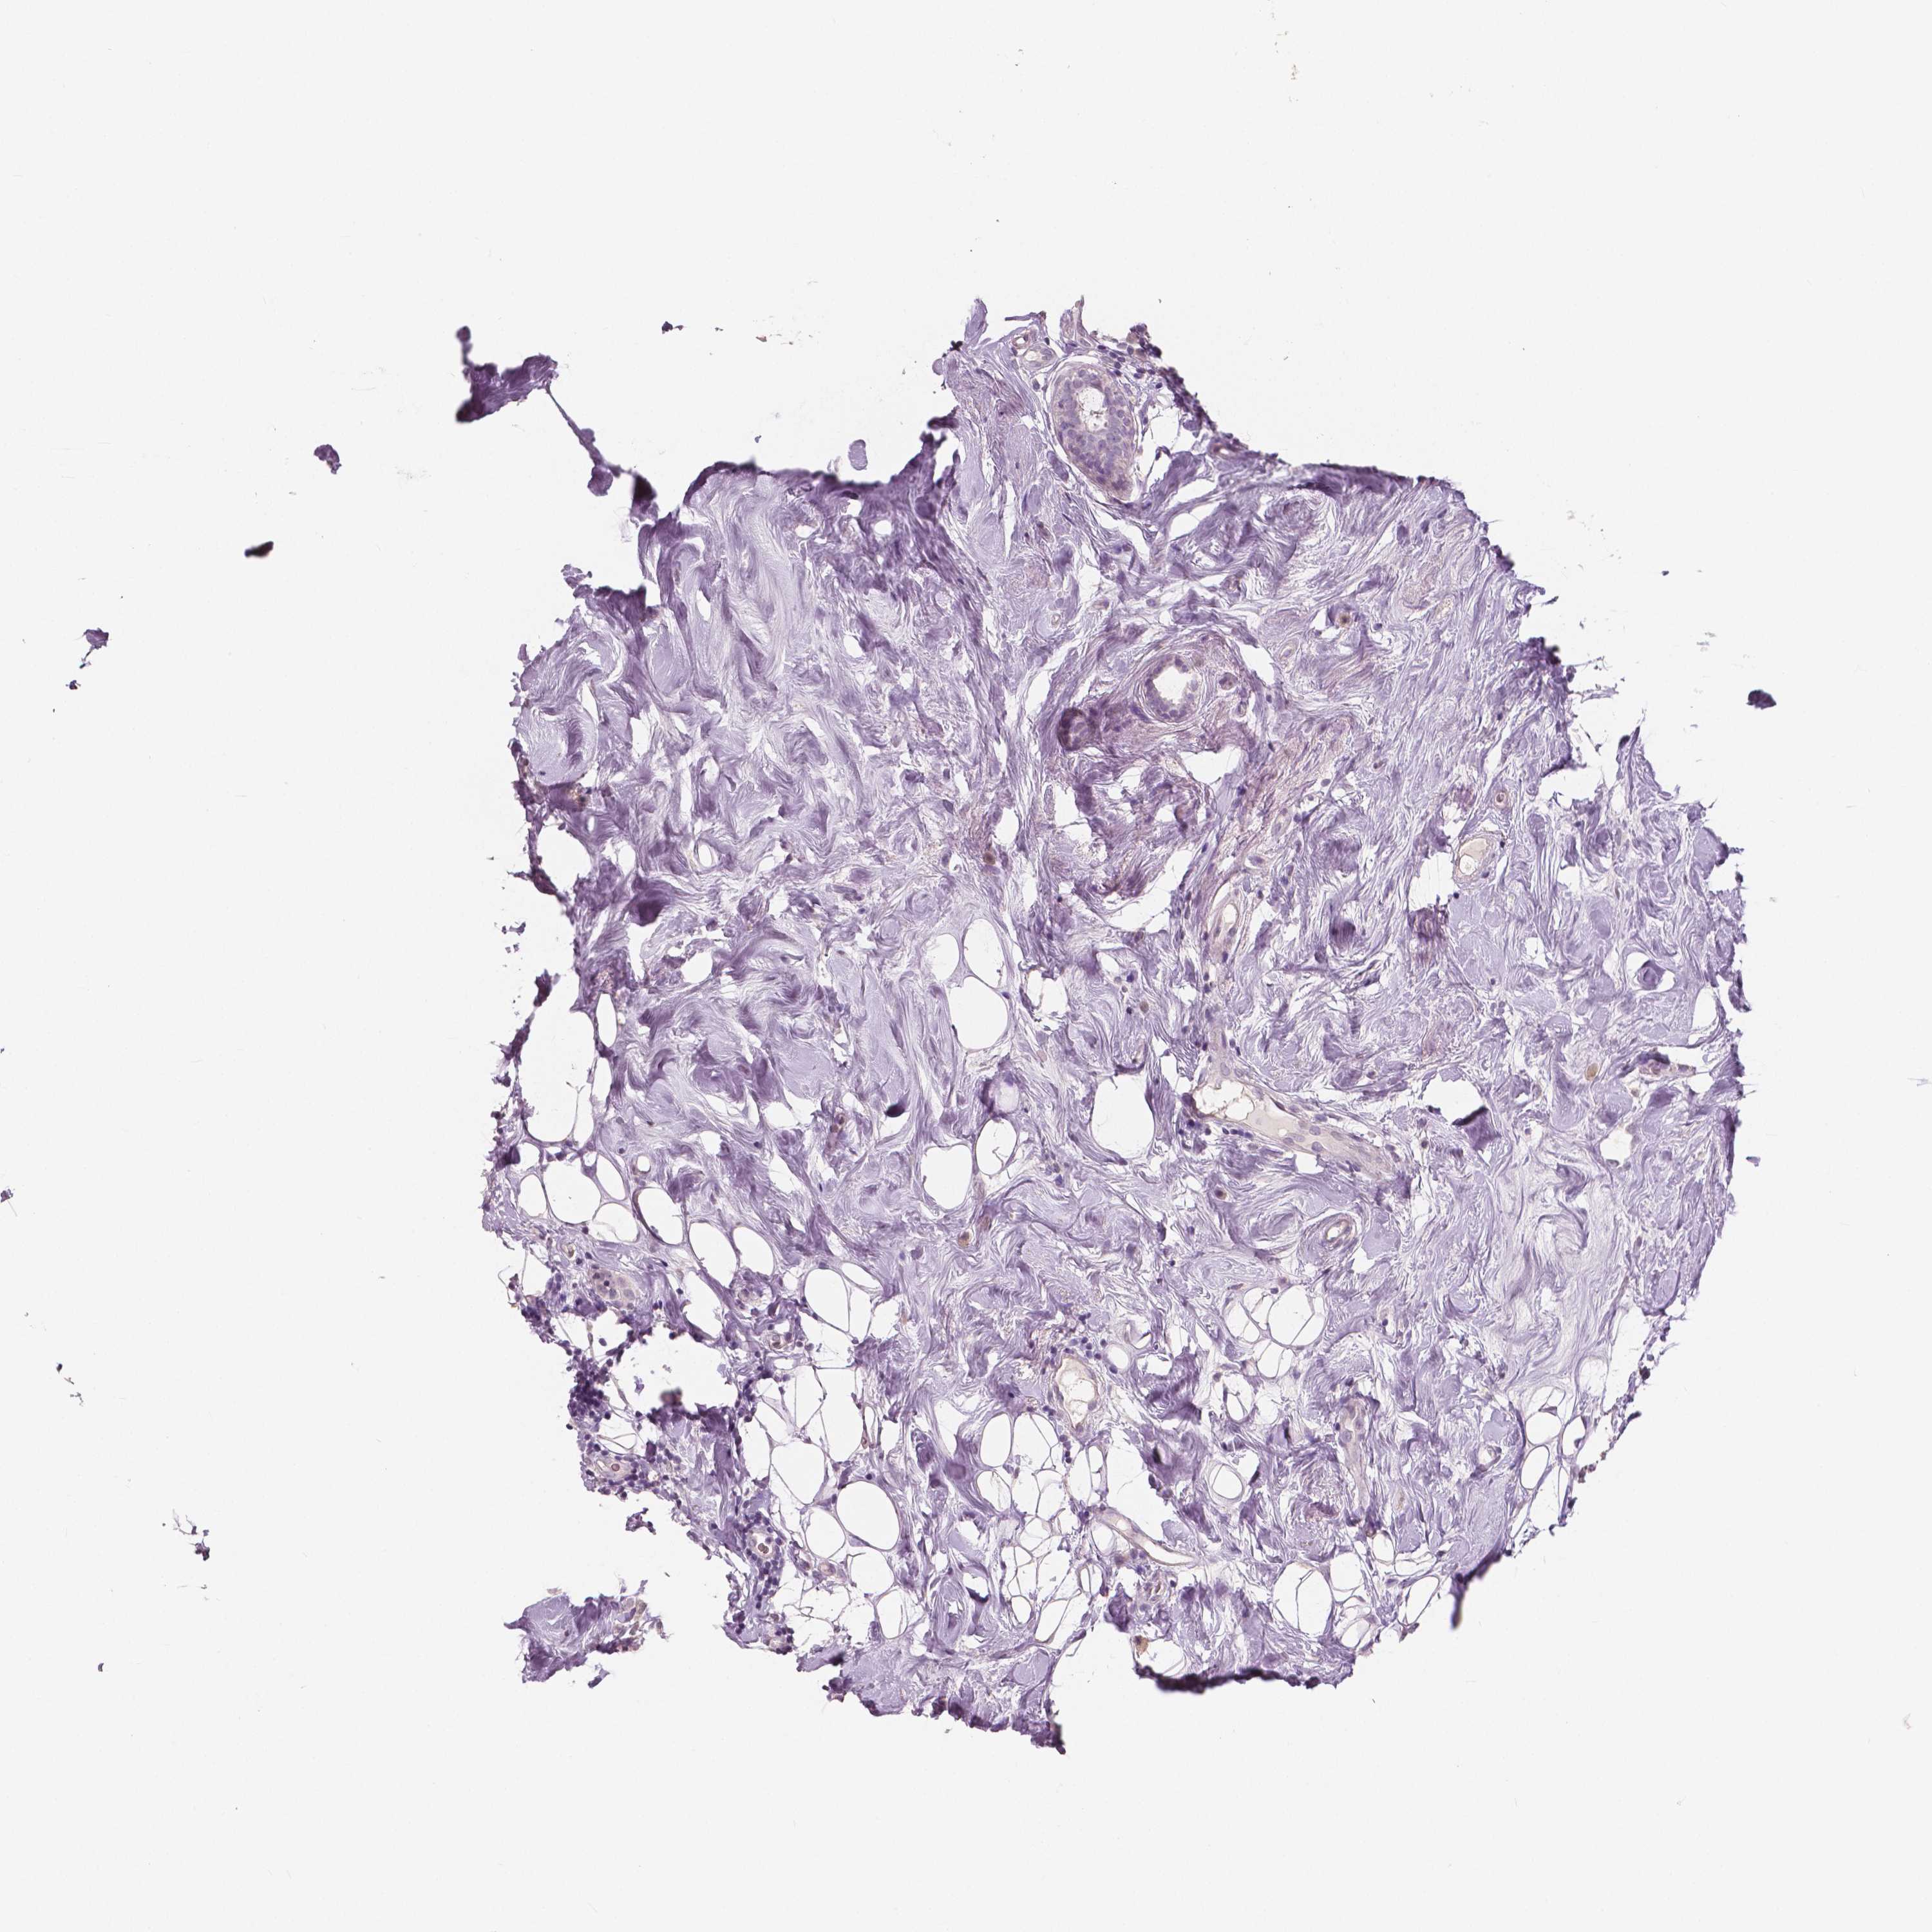

Breast cancer

Human cancer